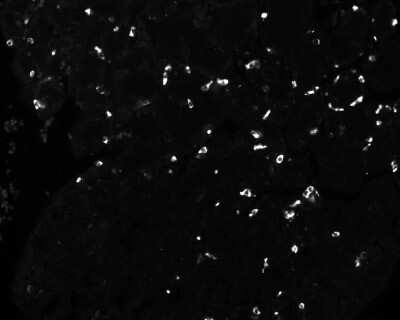

Immunohistochemistry-Paraffin: Chromogranin A Antibody (LK2H10 + PHE5 + CGA/414) - Azide and BSA Free [NBP2-34674] - Formalin-fixed, paraffin-embedded human small cell lung carcinoma stained with Chromogranin A MAb (LK2H10+PHE5+CGA414)